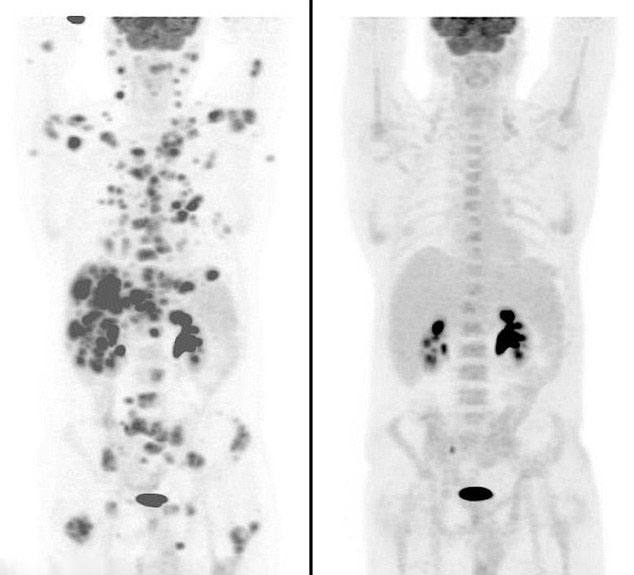

美男子服新藥12周清除70余腫瘤【圖】